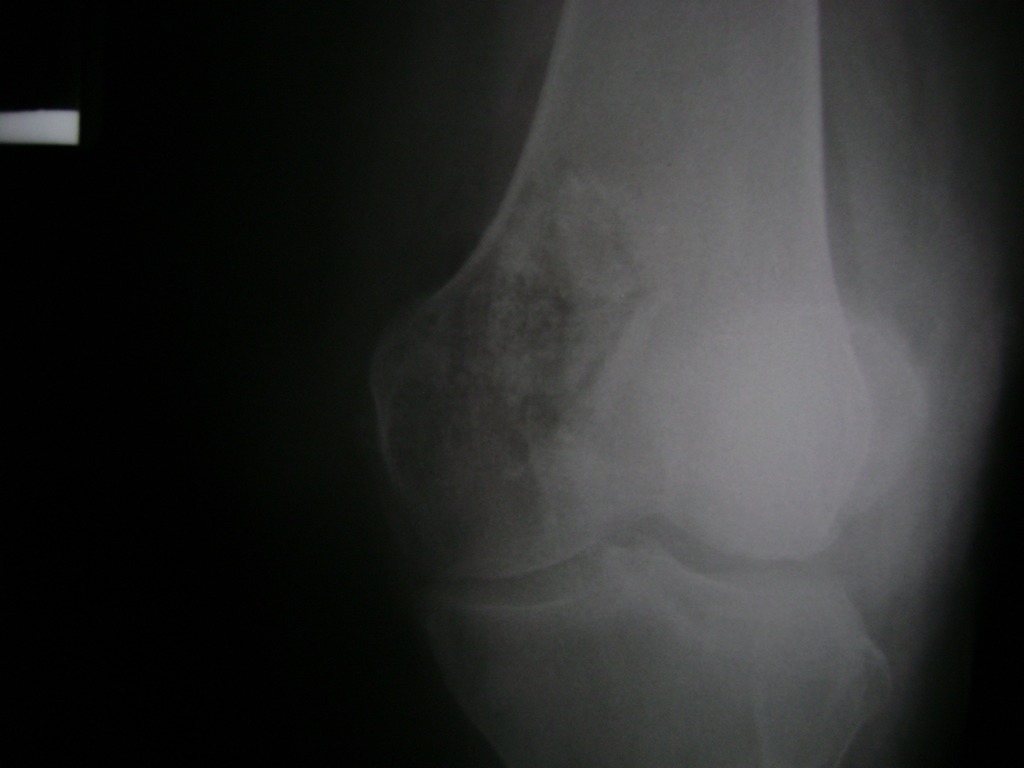

Fémur - Rodilla

La artroscopia de rodilla es un cirugía en el cual la estructura interna de la articulación es examinada ya sea para realizar un diagnostico o para realizar un tratamiento, este procedimiento se realiza utilizando un instrumento parecido a un pequeño tubo llamado artroscopio.